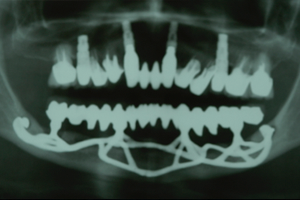

Figuras 7 e 8 – Controle clínico e radiográfico de 10 anos da nova reabilitação implantossuportada realizada pelo Dr. Sérgio Jayme, usando os mesmos implantes justaósseos inferiores realizados pelo Dr. Nilton De Bortoli, 40 anos antes.